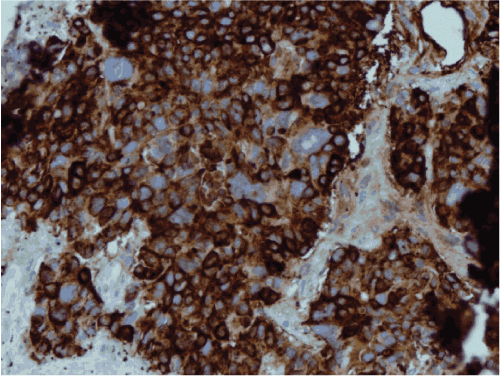

Chromogranin

Figure 8: Chromogranin positivity in solid area.